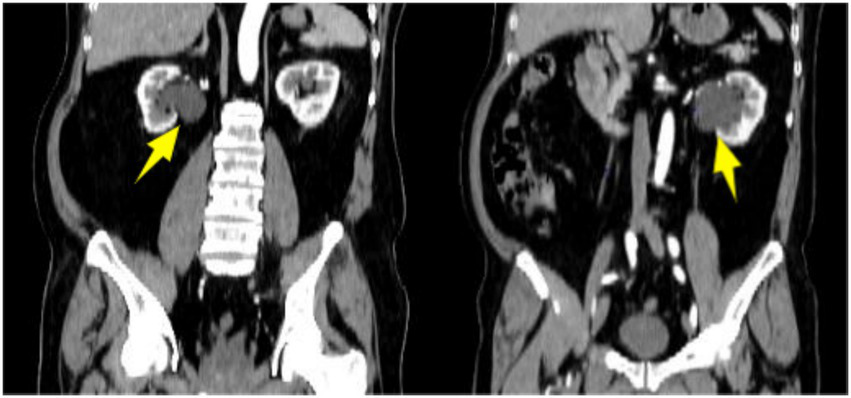

Abdominal non-contrast and contrast-enhanced CT scans demonstrated normally sized kidneys with intact capsules. Minimal exudative changes were observed surrounding both kidneys. Both renal pelves contained cystic low-density lesions, measuring approximately 5 cm on the left and 4 cm on the right. No significant enhancement of the cyst walls or internal contents was seen during the delayed phase (Figure 1). Coronal reformatted images confirmed a larger left-sided cyst (Figure 2).

Figure 2

Coronal reformatted contrast-enhanced CT showing cystic low-density lesions in bilateral renal pelves (as indicated by arrows).